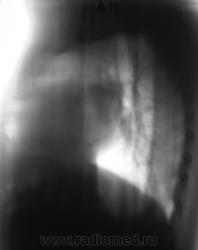

2. Конечно, мы на свой страх и риск, произвели дообследование, согласно стандарту. Итог дообследования представлен в серии 3.

Все признаки периферического рака...."расти" так может и лет пять...пока репу в диспансере будут чесать...

В заключении, именно однозначно, выставлен данный диагноз, изображения и все необходимое записано на диск. Это не ошибка для ООД. В ООД такой ошибки быть не может, ибо это специализированное учреждение.  Кстати, это, как Вы понимаете, случай не единичный.